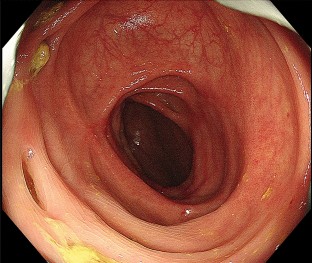

Lenvatinib is a standard molecular targeted agent for the first-line treatment of unresectable hepatocellular carcinoma. Here, we report a case of colitis induced by Lenvatinib treatment in a patient with hepatocellular carcinoma. A 78-year-old man previously treated with Lenvatinib for unresectable hepatocellular carcinoma was admitted to our hospital complaining of right lateral abdominal pain without diarrhea. Our endoscopic findings showed multiple ulcers and erosions on his ascending colon, and he was diagnosed with colitis induced by Lenvatinib treatment. After the discontinuation of Lenvatinib, his colitis improved, and he resumed Lenvatinib at a lower dose. Colitis is a rare adverse event of Lenvatinib, and this is the first detailed report of colitis induced by Lenvatinib with endoscopic findings.

Fig. 1